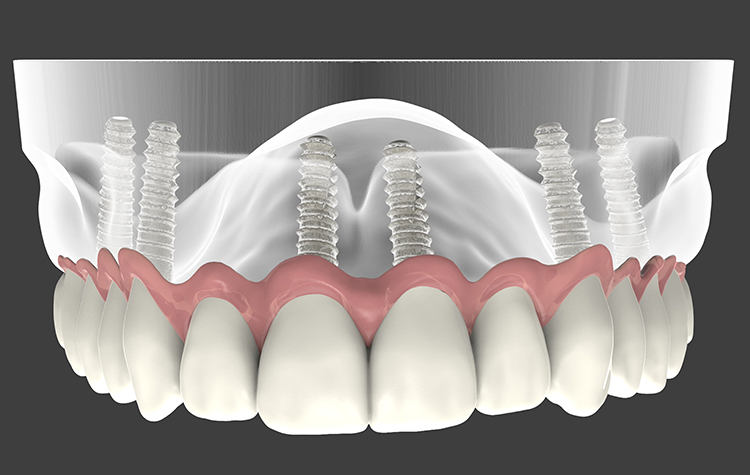

Dis Implantlari Sizin Icin Uygun Mu Saglik Haber

Dis Eksikligi Kaderiniz Olmasin Eskisehir Haberler

Dis Cektirmeden Curuklerden Kurtulmak Ve Implant Tedavisi Oncesi Dis Kurtarma Yontemleri Youtube